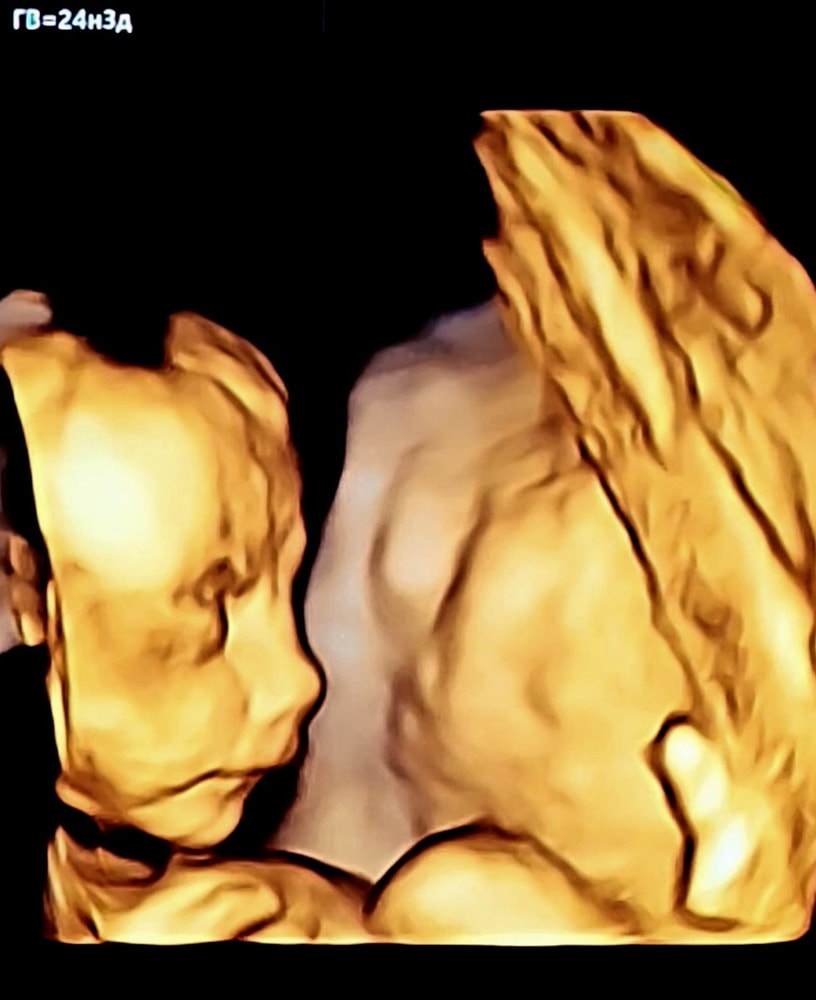

Теперь даже по профилю можно сказать, что он - вылитый муж. Нос, конечно, ещё изменится, но характерный изгиб уже виден 🥹

Не знаю, как описать это удивительное чувство. Слова "радость", "гордость", "восторг" не отражают и 10% того, что я чувствую, наблюдая их сходство. Я буквально создаю копию самого лучшего, самого любимого человека на свете 🥹 Теперь понимаю, откуда берутся Иван Иванычи🥰

Ну и самый трогательный материнский момент для меня: сын не любит УЗИ, пытается закрыться, но в этот раз я стала ворковать с ним, уговаривая сделать фото для бабушек и дедушек. И он перестал отворачиваться и... улыбнулся 🥹🥹🥹